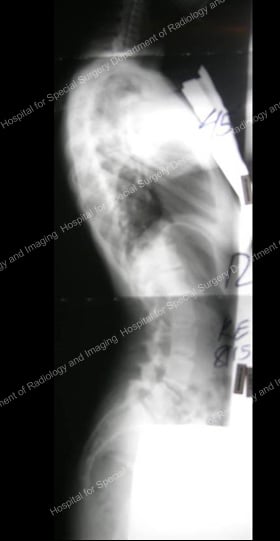

Figures 9 & 10: Presurgical posterior and anterior X-rays – scoliosis requiring anterior approach.